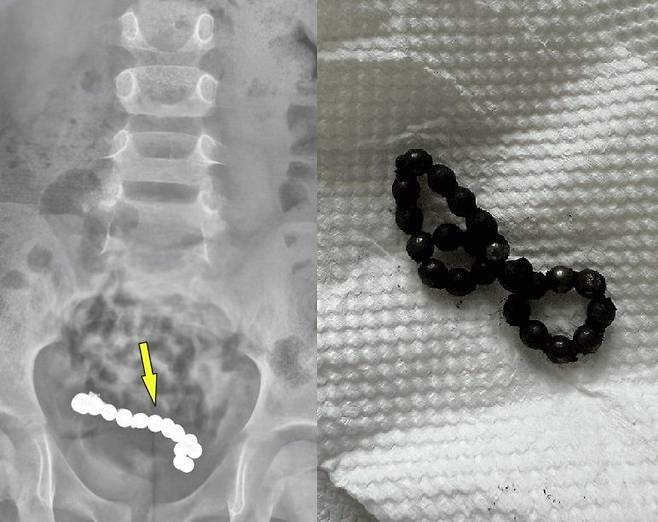

초기에는 단순 변비로 판단돼 관련 치료를 받았지만, 증상이 호전되지 않았다. 이에 추가로 엑스레이 검사를 받은 결과, 하복부에 동글한 이물질이 여러 개 붙어 있는 것을 확인했다.

현지 소아과 병원 의료진은 복강경 수술을 진행했고, 소년의 뱃속에서 22개의 자석이 발견됐다. 이 자석들은 서로 붙어 팔찌처럼 보이는 상태였다.